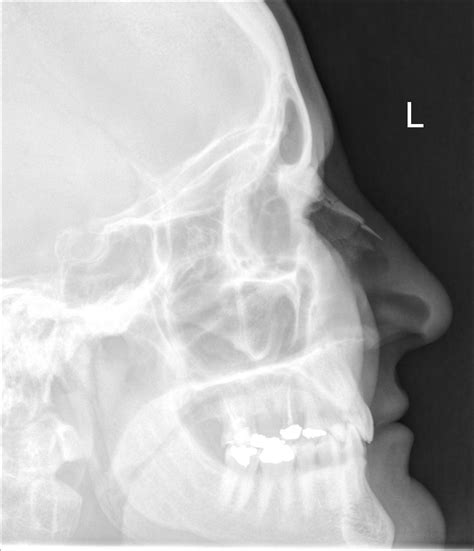

Diagnosing a Minor Nose Fracture

Diagnosing a minor nose fracture typically involves a physical examination and imaging tests. The healthcare provider will:

• Order imaging tests, such as X-rays or CT scans, to confirm the fracture and assess its severity.

Imaging tests are crucial for determining the extent of the fracture and planning the appropriate treatment.